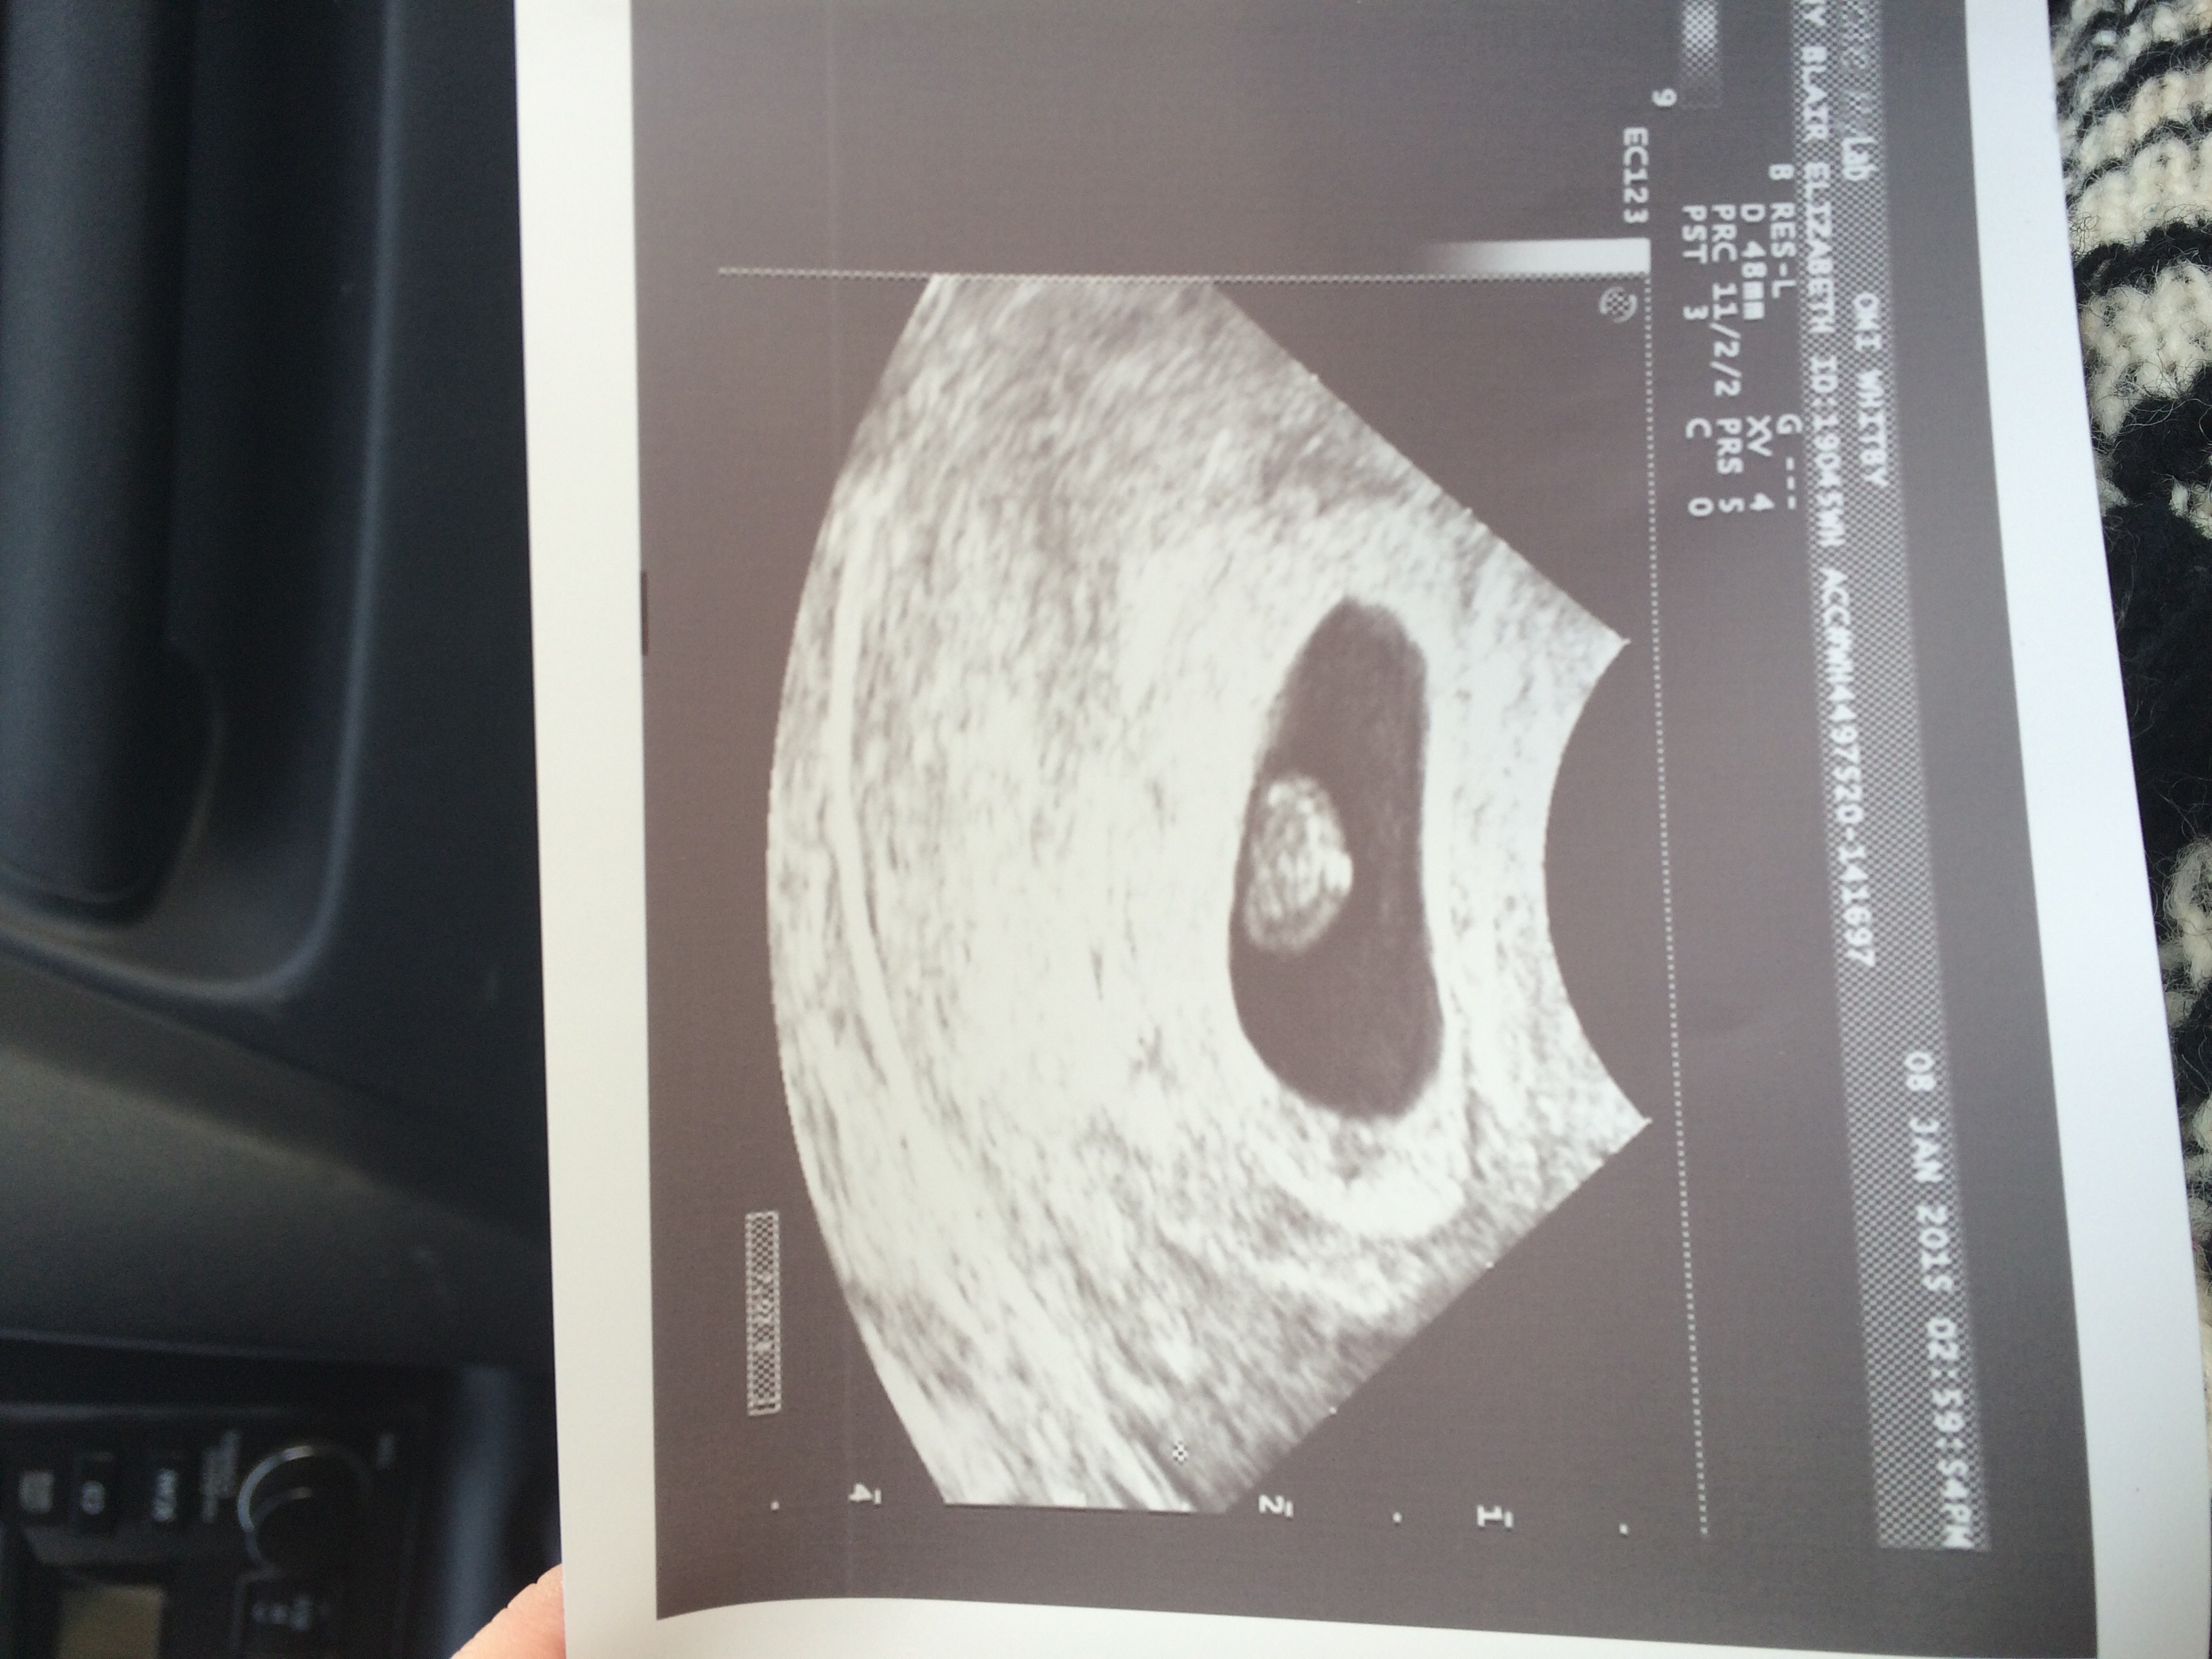

8 weeks 6 days! Heartbeat 169!

Due Date Aug 17!